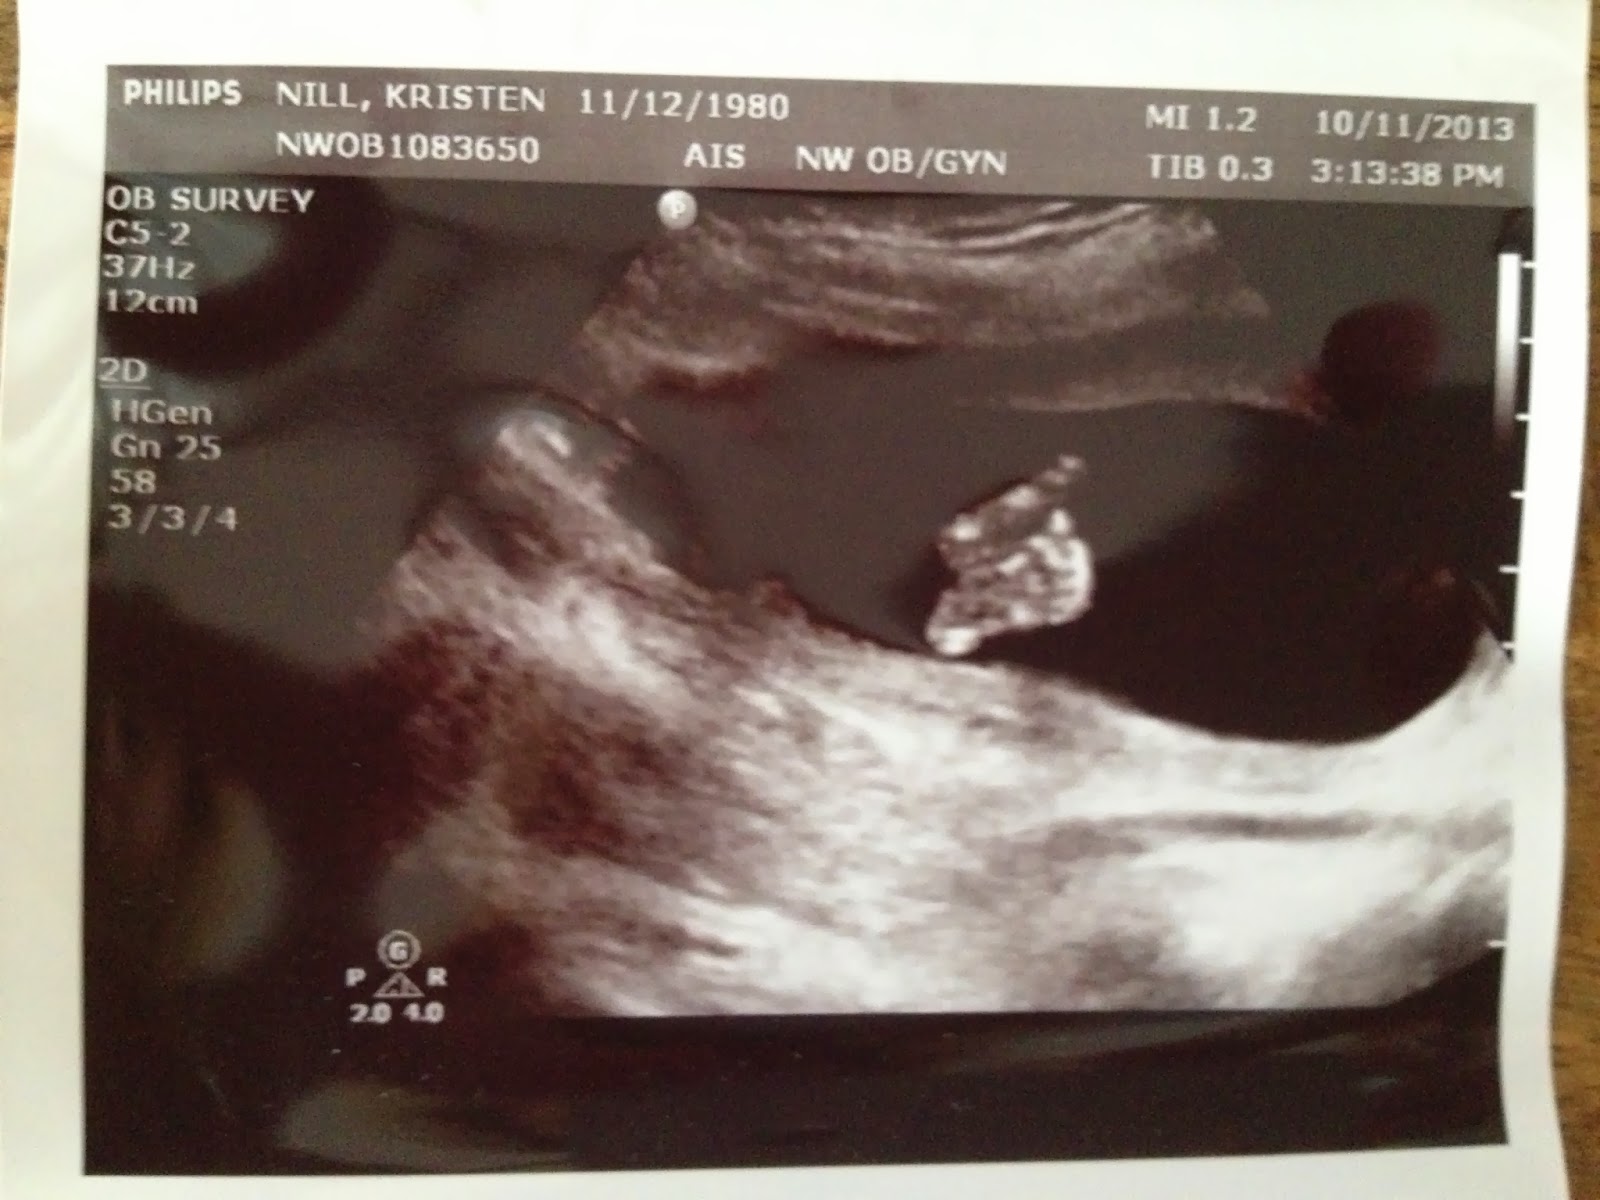

And little feet:

It’s just so dark in there. And can you imagine how cramped? No thanks.

So there’s been a lot of baking going on in the Nill house lately. In fact, I’ve been baking up a storm for a little over three months now. Like, 24/7. It’s a very time-consuming recipe that I want to make sure to get just right because I’ve got a yummy little…

in my

!!!

The timer will ding sometime around 3/12/14 and we will have another new Nill on our hands! Baby boy or baby girl we don’t know yet, or if we will even find out, but we are so excited to announce that Ashton is going to be a big brother. He is, of course, completely unaware of this fact. At some point we’ll have to start talking about it to prepare him but for now, ignorance is bliss.